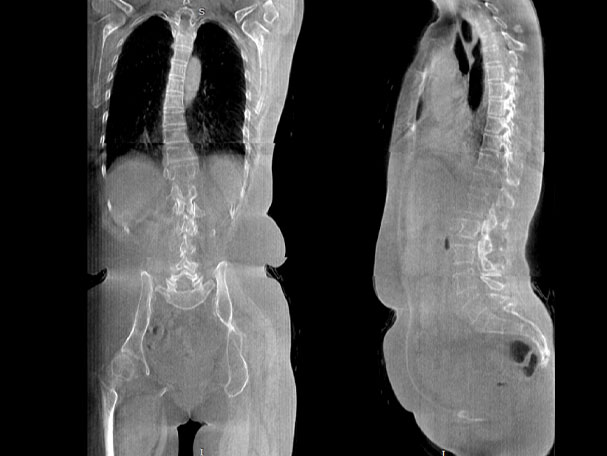

• 全身姿态评估

WR-3D能提供一种负重位状态下全身的姿态和三维空间任一平面平衡评估,使全脊柱术后评价更客观、真实 。通过各种临床参数包括骨盆、脊柱参数评价骨盆、脊柱平衡,避免由于髋膝屈曲造成的代偿性脊柱失衡的发生,WR-3D提供了三维空间任一平面平衡评估测量方法,可以更加定量地评估手术效果 。

FOV最大350mm

支持双腿或双侧髋关节扫描 | 方便对比,降低漏诊误诊

FOV 250mm

FOV 350mm